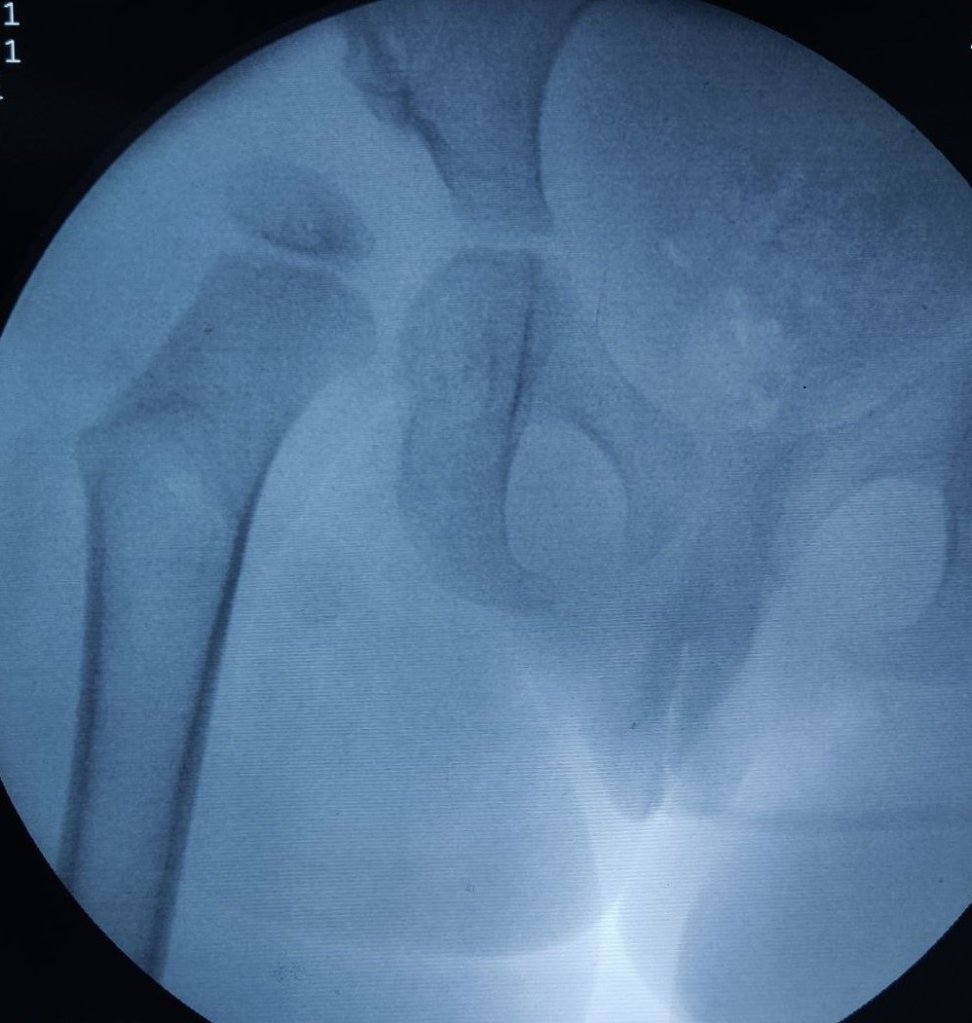

Arthrogram is an excellent tool to evaluate the state of cartilage over the lateral aspect and superolateral aspect of femoral head and then decide whether we want to do the acetabular osteotomy at the same sitting or defer it.

Illustrating below a case whether the Derotation osteotomy was done first and the we decided the acetabular osteotomy based on the cartilage cover on arthrogram.

This is useful in a child younger than 2 and half years as acetabulum has good remodelling potential at that age. In older children we will need to combine the procedures.

The state of hip before the osteotomy. Open reduction was done elsewhere about a year ago. Persistent hip dysplasia was observed.

The Derotation osteotomy improved the coverage but we still have to decide about the acetabular procedure.

An arthrogram reveals a large cartilage cover on superolateral acetabulum. The cartilage bump is pointed to by the forceps.

The C Arm image is superimposed and an artist’s impression is drawn showing what the cartilage would look like in 3D. This offers an excellent teaching tool and a 3D orientation for young surgeons and pediatric orthopedic trainees to decide whether an acetabular osteotomy is needed

The surgeon would then discuss with parents and opt to continue an acetabular procedure of take a staged approach